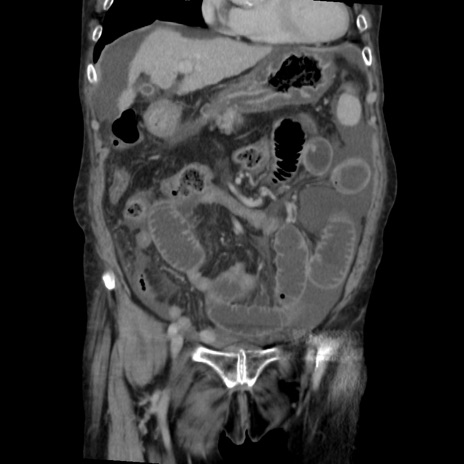

矢状断像